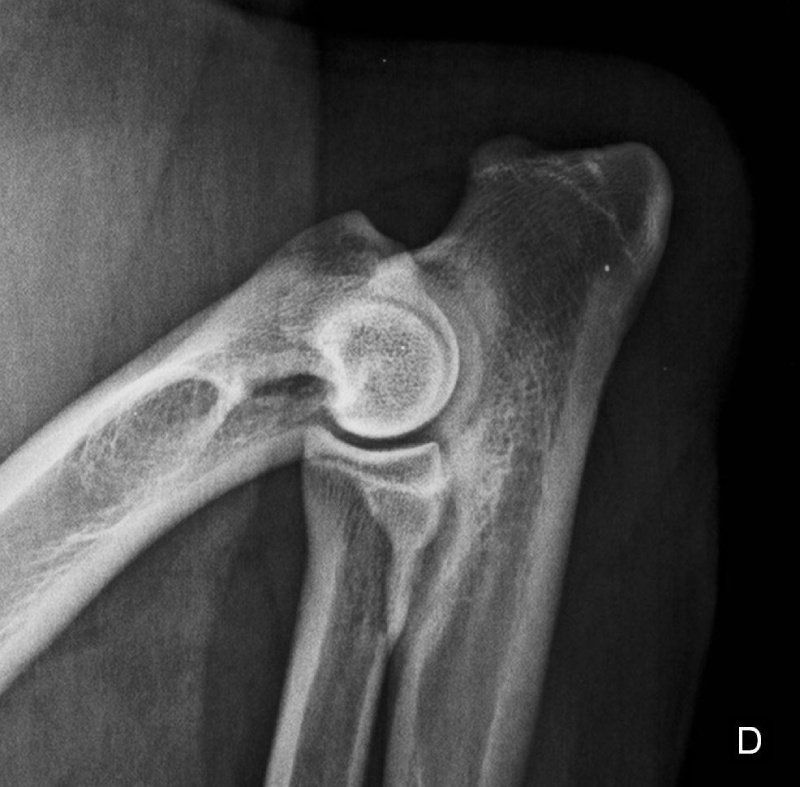

Offriamo i servizi che solo dei veri professionisti seri e qualificati del settore possono assicurare, così che i tuoi amici a quattro zampe possano godere sempre di buona salute. Ci occupiamo anche di eseguire studi radiografici ufficiali per le patologie scheletriche ereditarie, come ad esempio la displasia dell'anca o del gomito.